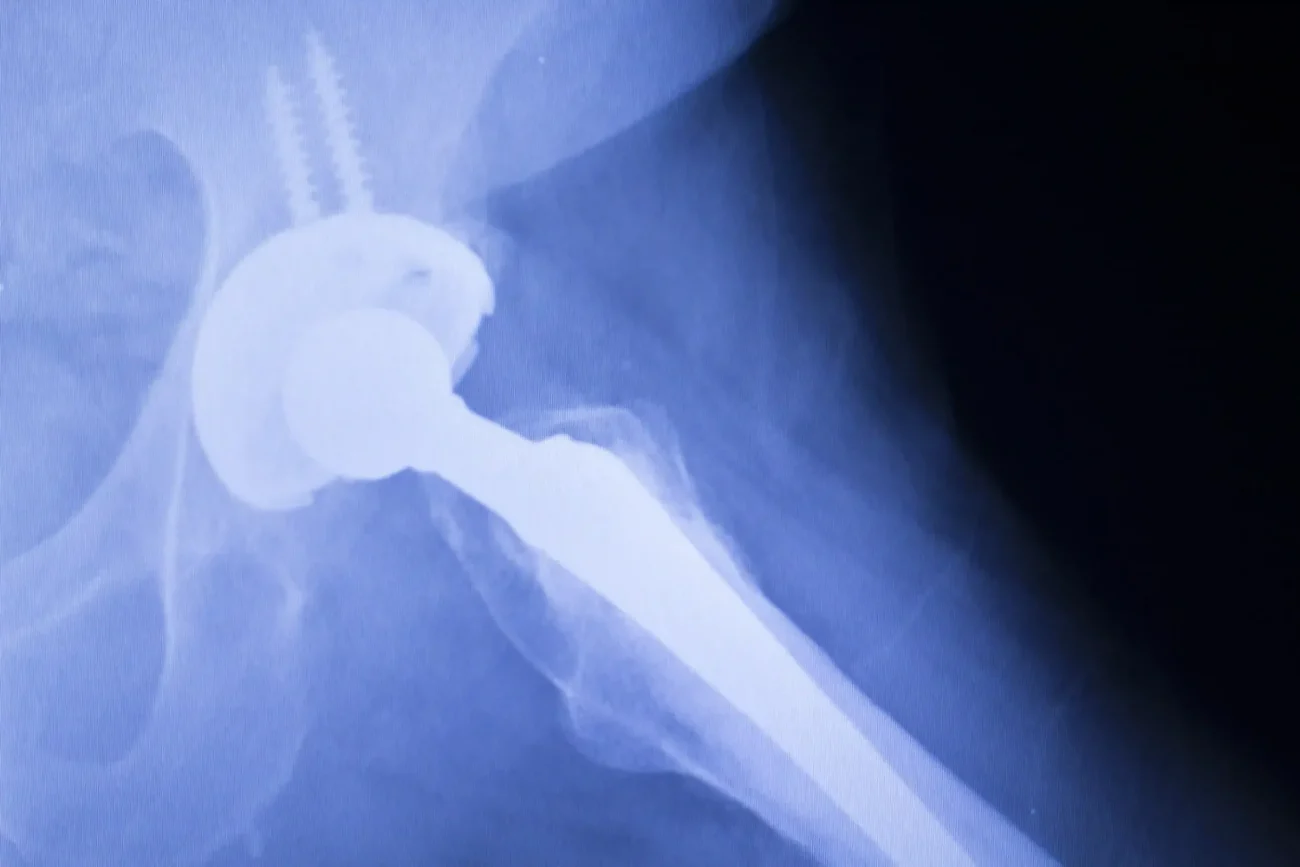

Hip replacement surgery is meant to restore mobility and improve quality of life, but when an implant fails, it can lead to severe pain, mobility issues, and the need for corrective surgery.

- Need for Revision Surgery: Additional procedures to replace or repair failed implants.

Hip Replacement Recall Information

Several hip replacement devices have been linked to high failure rates, severe complications, and the need for revision surgery. While some of these implants have been recalled, others remain on the market despite ongoing concerns [8].